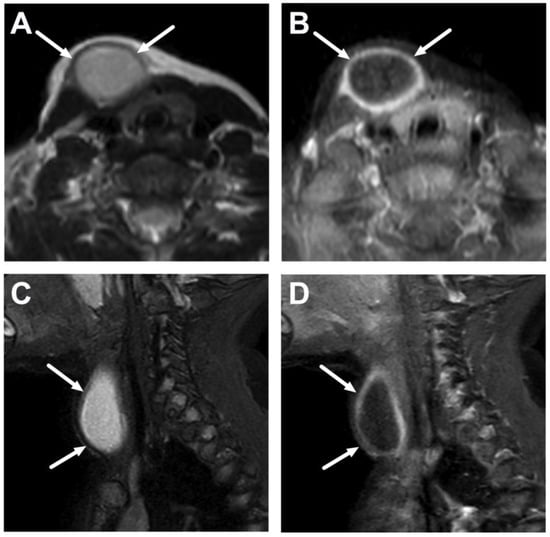

5.2. Cystic Masses